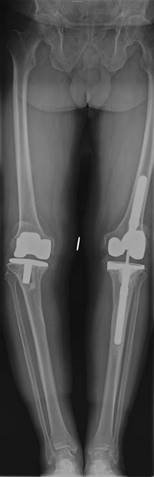

This is a picture of a 67-year-old woman with a painful left knee. The pain has been increasing over the last 3 years. She is otherwise fit and well and has had previous joint replacements as shown.

How would you manage this patient?

How would you consent the patient for a TKR?

Describe your plan for surgery in this case.

I would establish from the history more about her pain, disability, and what treatment she has so far received. On examination I would look at the nature of the deformity, whether it is correctable, the integrity of the medial collateral ligament, patella tracking, and neurological status (common peroneal nerve). I would examine her hip and foot. I would arrange some radiographs including standing AP, lateral. Von Rosenberg views and a skyline patella can be useful with valgus deformities. I may want a long leg fi lm.

T reatment would include maximizing conservative measures. If this failed I would discuss with the patient knee arthroplasty surgery (lateral unicompartmental or total).

I would describe the procedure as well as alternative treatments. I would describe the anticipated outcome in terms of pain relief; functional outcome, and longevity. I would explain the risks and complications of the surgery. General risks and specifi c risks for TKRs as well as specifi c risks for valgus TKRs.

Describe your plan for surgery in this case. z Correct indications met z Patient fully consented z Antibiotic prophylaxis z Choice of implant z Choice of approach z Principles of bony cuts, especially rotation of femoral componentโ h ow I will assess this (hypoplastic or wear on posterior lateral femoral condyle makes posterior referencing inaccurate)

z What I will do with the patella z Soft tissue balancing (sequence of releases) z Implantation of prosthesis and cementing technique z Drain?

z Post-operative management and DVT prophylaxis z Follow-up